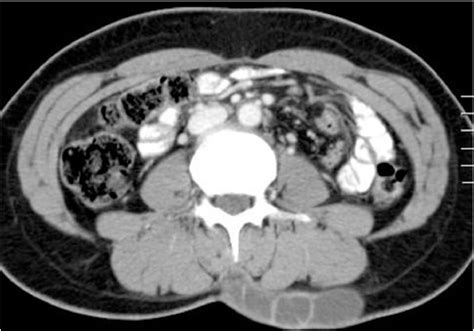

During the consultation, your surgeon will likely perform a physical examination and, in some cases, order an ultrasound to determine the depth and vascularity of the cyst. This helps in planning the incision size and determining whether local anesthesia will suffice or if a more comprehensive setting is required.